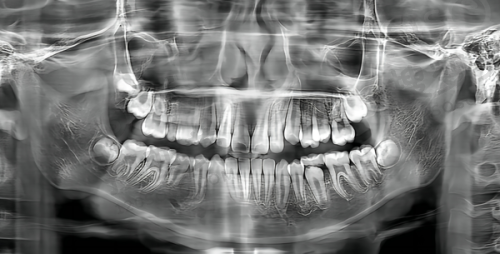

店内配备了优等的诊疗设备,像数字化口腔扫描仪、CBCT等。这些精良的设备能够确保牙齿种植手术的精细性与安心性,让患者在种牙过程中更加放心。而且,中山公园店汇聚了一批口碑良好的种牙医生,以华医生为代表,他们擅长运用微创技术进行即刻种植与全口种植。这种技术大大缩短了患者的变好周期,减少了患者在治疗过程中的不适感。

松丰口腔医院拥有一支由资历深口腔医师组成的医疗团队,配备了国内外靠前的口腔诊疗设备,提供多方面的口腔治疗服务,尤其在种植牙和正畸领域享有盛誉。在种植牙方面,该医院引进了一系列国内外靠前的口腔诊疗设备,如3D口腔CT、数字化种植导航系统等,为种植牙手术提供了精细、安心的保护。